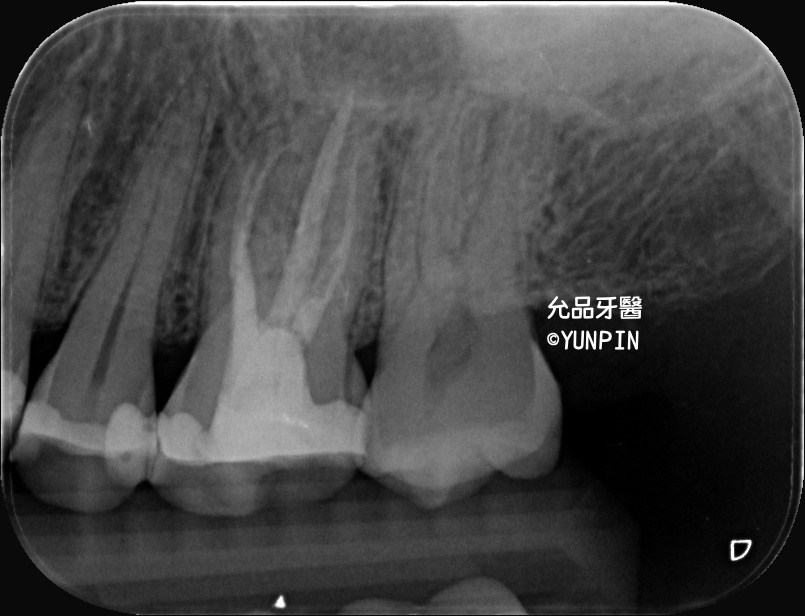

齒槽骨脊保存術socket preservation

患者主訴牙痛,他家診所檢查為牙裂,口內實際狀況已有明顯裂痕

討論完建議施作齒槽骨脊保存術,保留牙窩空間以利後續重建。